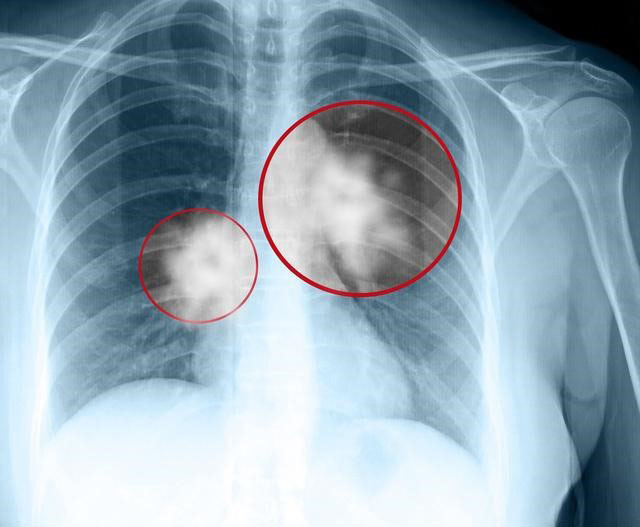

头痛|肺癌脑转移至少缩短一半生存预期,有哪些措施可以预防脑转移

肺癌非常容易出现脑部转移,有学说认为肺癌细胞有一定的嗜中枢神经的特点,不过这个学说需要进一步论证。目前比较公认的理论认为是肺血管与椎体静脉系之间存在交通支,肺癌细胞可以不经过肺部毛细血管的阻滞和过滤功能,直接通过血液循环进入大脑,从而发生脑转移。

肺癌病人中尤其是小细胞肺癌更容易出现脑转移,所以一旦确诊肺癌,即便进行了根治性手术,在后期的随访复查过程中也需要常规进行头颅CT或者磁共振检查。脑转移出现后就意味着肺癌晚期,预后比较差,治疗上主要采用全脑放疗或者立体定向放疗,可以口服替莫唑胺化疗,基因检测突变者可以考虑口服小分子靶向药物治疗。